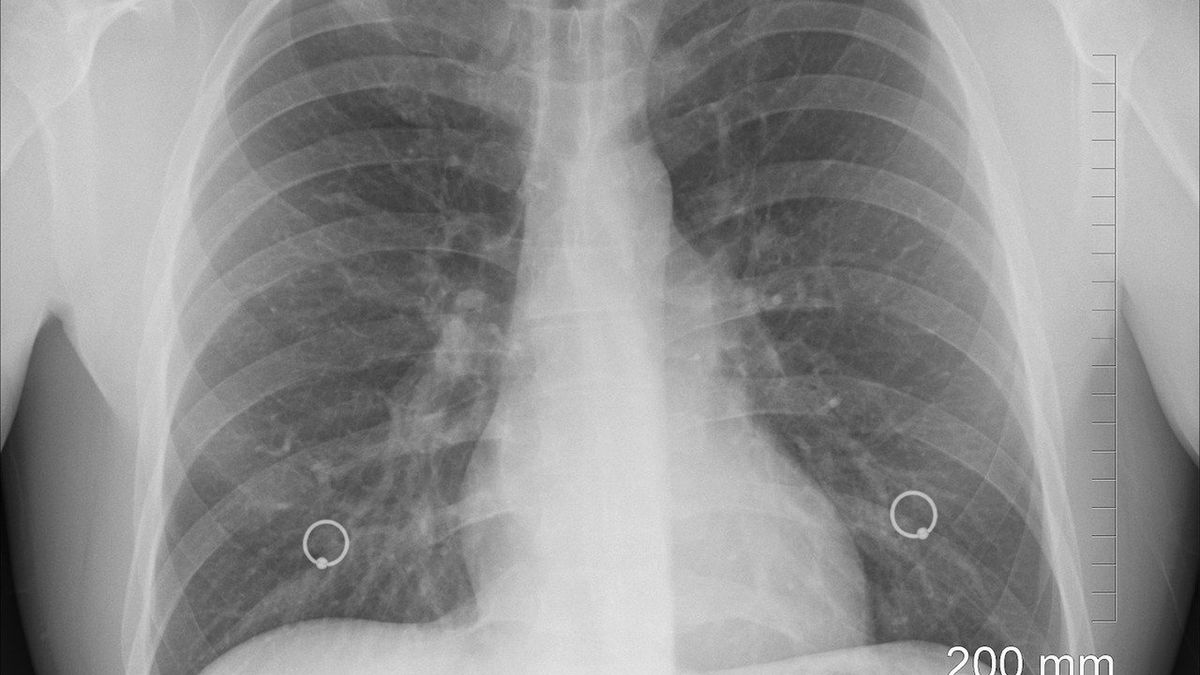

W tej chwili koronawirusa wykrywa się za pomocą testów w postaci wymazu nosowo-gardłowego. Problem w tym, że ta metoda nie jest w pełni skuteczna. Lekarze z Turynu twierdzą, że testy nie wykrywają około 20 proc. zakażonych.

Włosi mają skuteczniejszą metodę. Ich zdaniem badanie USG płuc jest lepsze, bo pozwala od razu wykryć koronawirusa. Badania są optymistyczne i potwierdzają ich tezę.

Przebadano 228 pacjentów, którzy mieli objawy COVID-19. Tradycyjne testy w 107 przypadkach dały wynik pozytywny. Po zastosowaniu USG płuc okazało się, że zakażonych jest o 21 osób więcej. Wcześniej u tych pacjentów wymaz był negatywny.

Stosowanie USG płuc przy diagnozowaniu zakażonych może być kluczowe w zwalczaniu pandemii. Dzięki temu chorzy od razu zostaną odizolowani i nie będą zakażać. Testy sprawiają, że niewielki procent ludzi nieświadomie staje się nosicielami.